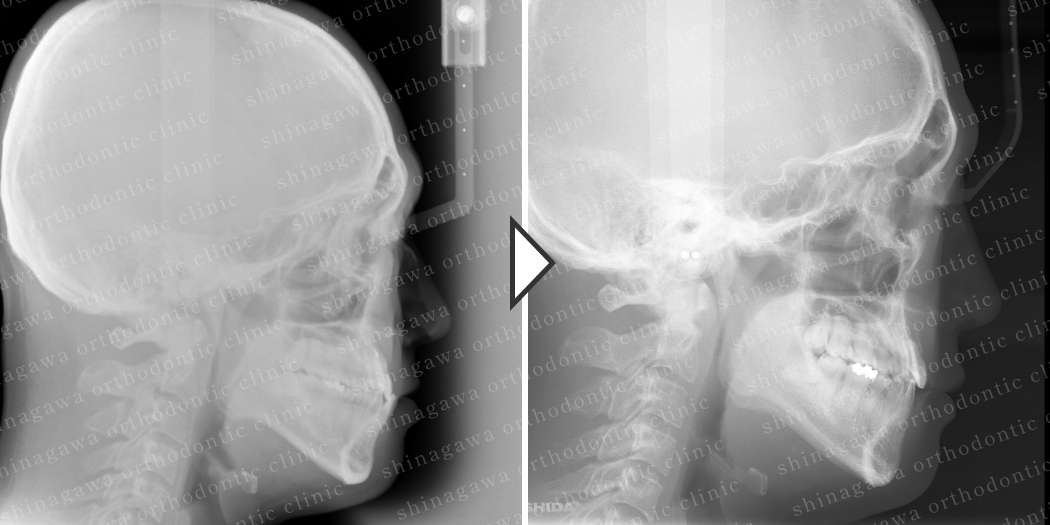

症例8

上顎前突、叢生

| 年齢 | 28 歳 |

|---|---|

| 性別 | 女性 |

| 住所 | 東京都大田区 |

| 主訴 | 出っ歯 |

| 不正咬合の種類(診断) | 上顎前突, 叢生 |

| 装置 | 表ワイヤー |

| 抜歯/非抜歯 | UR4, UL4 |

| 期間 | 20M |

| 費用 | 935,000 円 |

| リスク・副作用 | 矯正治療による歯の移動に伴う痛み, 虫歯, 歯肉退縮, 歯根吸収 |